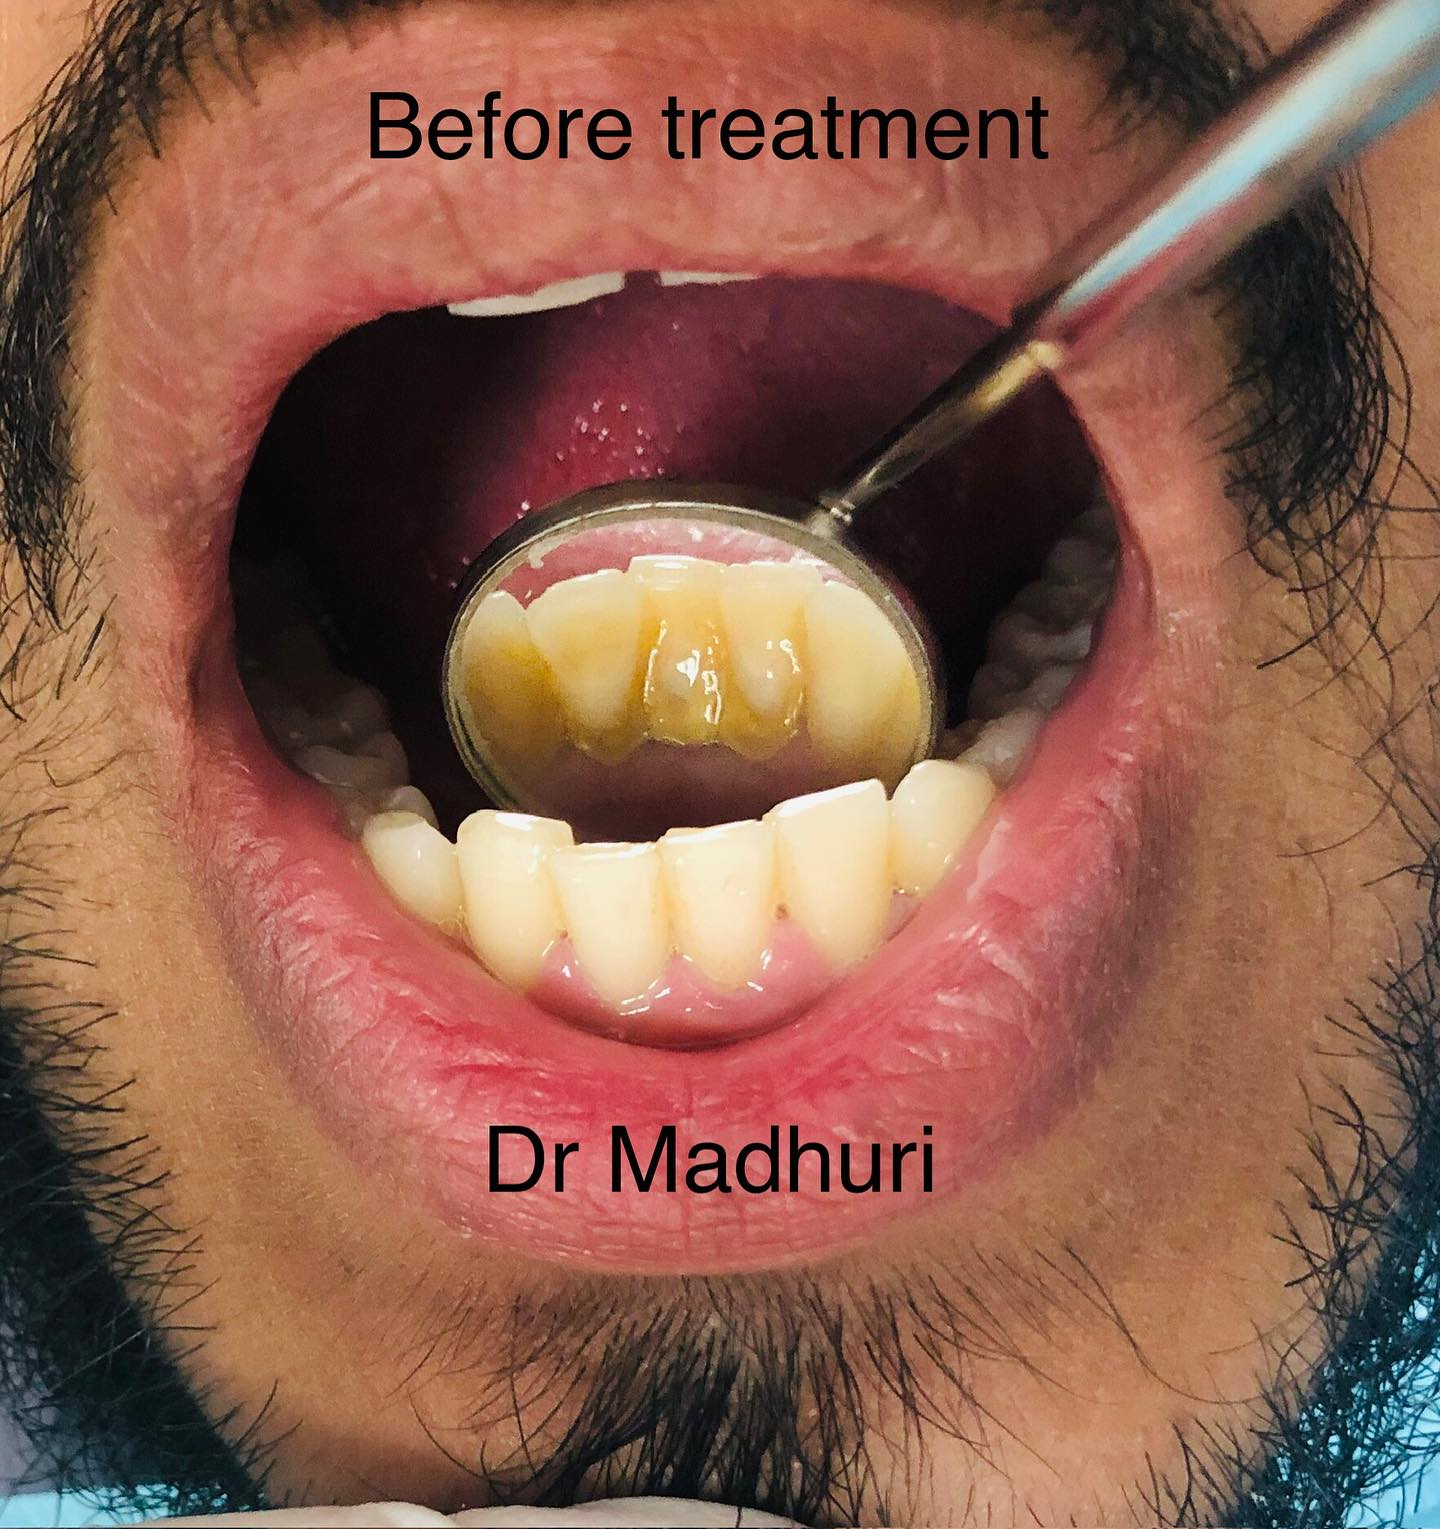

Explore Our Clinical Dental Gallery

Welcome to our official treatment gallery, showcasing the real results, smile transformations, and advanced dental care delivered by Dr. Madhuri. We believe that a picture is worth a thousand words when it comes to the art and precision of modern dentistry. Review our comprehensive visual portfolio below to see how our dedicated care helps patients achieve healthy, beautiful, and confident smiles.